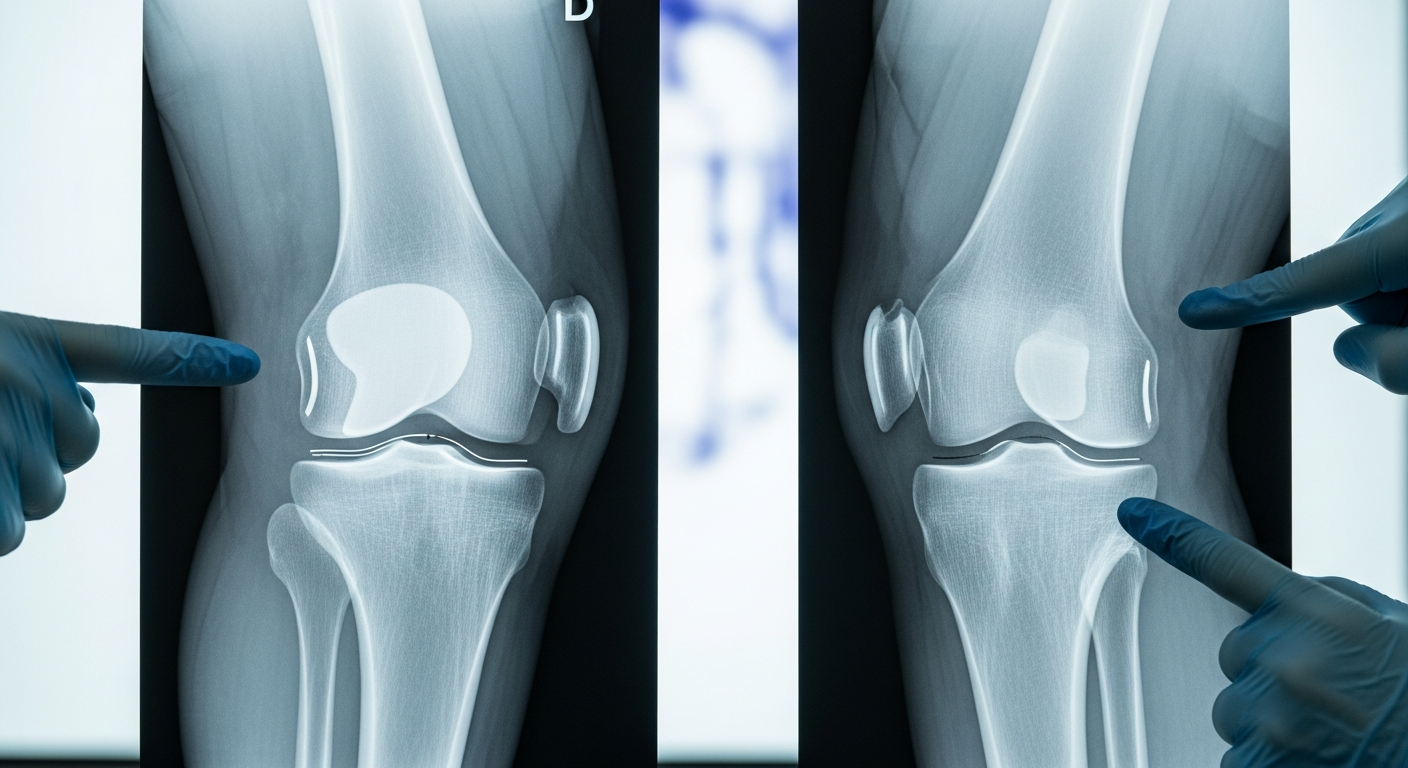

Although contemporary knee prosthesis have proven reliability and efficacy in treatment of knee oste ...

ABSTRACT Biomechanically knee joint has a motion complex includes gliding, rolling, translation and ...

Amaç: Unikondiler diz artroplastisinde (UDA) aseptik gevşeme başarısızlığın en önemli nedenlerind ...